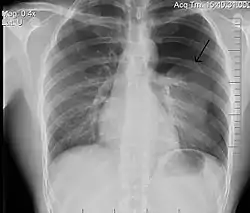

![]() تبين الأشعة السينية للصدر وجود استرواح الصدر على اليمين (يسار الصورة)، حيث تبين أيضًا غياب علامات الرئة لوجود هواء حر داخل الصدر. A large right-sided spontaneous pneumothorax (left in the image). An arrow indicates the edge of the collapsed lung | |

الأشعة السينية على الصدر

عادة ما يكون التصوير الشعاعي العادي للصدر، بإشعاع الأشعة السينية من الخلف (من الخلف للأمام) هو أنسب فحص في البداية. وعادة ما يتم تنفيذ ذلك خلال الشهيق (مع كتم النَفَس). لأن التصوير بالأشعة السينية أثناء الزفير (بعد خروج الهواء) لا يعطي أي معلومات إضافية.[12][13] إذا لم تُظهر الأشعة السينية الساقطة من الخلف للأمام استرواح صدري، ولكن كان هناك شكوك قوية في وجوده، يتم عمل أشعة سينية جانبية ( بإسقاط الأشعة من الجانب)، ولكن هذه ليست الطريقة الروتينية.[13][17] ومن المألوف وجود انحراف المنصف (التركيب بين الرئتين التي يحتوي على القلب، والأوعية الدموية الكبيرة، والممرات الهوائية الكبيرة) بعيدا عن الرئة المتضررة بسبب اختلافات الضغط. لذا فإن هذا الانحراف ليس دليلا على حدوث استرواح الصدر الضاغط، إنما يتحدد أساسا عن طريق مجموعة من الأعراض بالإضافة إلى نقص الأكسجين، والصدمة.[12]

يمكن تحديد حجم استرواح الصدر (أي حجم الهواء في الفضاء الجنبي) بدرجة معقولة من الدقة عن طريق قياس المسافة بين جدار الصدر والرئة، ويتم على أساسه تحديد العلاج، لأنه يتم التعامل مع وجود استرواح صدري أصغر بشكل مختلف. وجود طبقة رقيقة من الهواء حجمها 2 سم يعني أن استرواح الصدر يحتل حوالي 50٪ من نصف الصدر.[13] وقد ذكرت المبادئ التوجيهية المهنية البريطانية أن القياس يجب أن يتم على مستوى باب الرئة (مكان دخول الأوعية الدموية والمسالك الهوائية في الرئة) باعتبار 2سم كنقطة فاصلة،[13] في حين تنص المبادئ التوجيهية الأمريكية أن القياس ينبغي أن يتم من قمة الرئة مع التفريق بين استرواح الصدر "الصغير" و "الكبير" بفاصل 3سم.[23] ولكن قد تبالغ الطريقة الأخيرة في حجم استرواح الصدر إذا كان يقع أساسا في القمة، وهو أمر شائع.[13] الروابط بين طرق القياس المختلفة ضعيفة، ولكن هي أفضل الطرق المتاحة السهلة لتقدير حجم استرواح الصدر.[13][17] يمكن أن يساعد المسح المقطعي (انظر أدناه) في تحديد حجم استرواح الصدر بدقة أكبر، ولكن لا يوصى باستخدامه الروتيني مع هذه الحالات.[23]